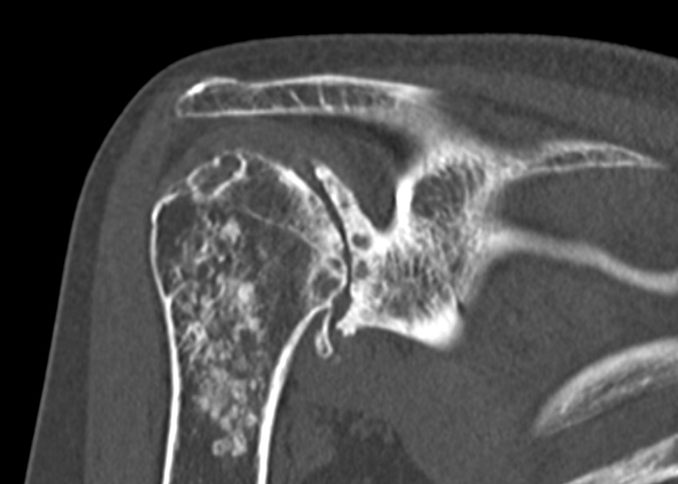

Coronal CT

深いお椀のような関節窩